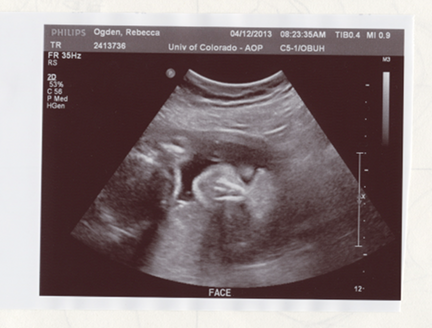

We watched Xavier's heart beating, saw his hands and arms, saw his feet and knees, saw his partly full bladder, his stomach, his rib cage. Even got a good view of the placenta. We got to view him from many angles today. It was as when you wait for a good friend to deplane: you wait and watch and wait and scan, and then you see them and you smile with great joy.

A profile of Xavier. You can see one of his hands below his chin and a good shot of his nose.

This is a nice shot of Xavier's face from an angle looking from the top of the head.